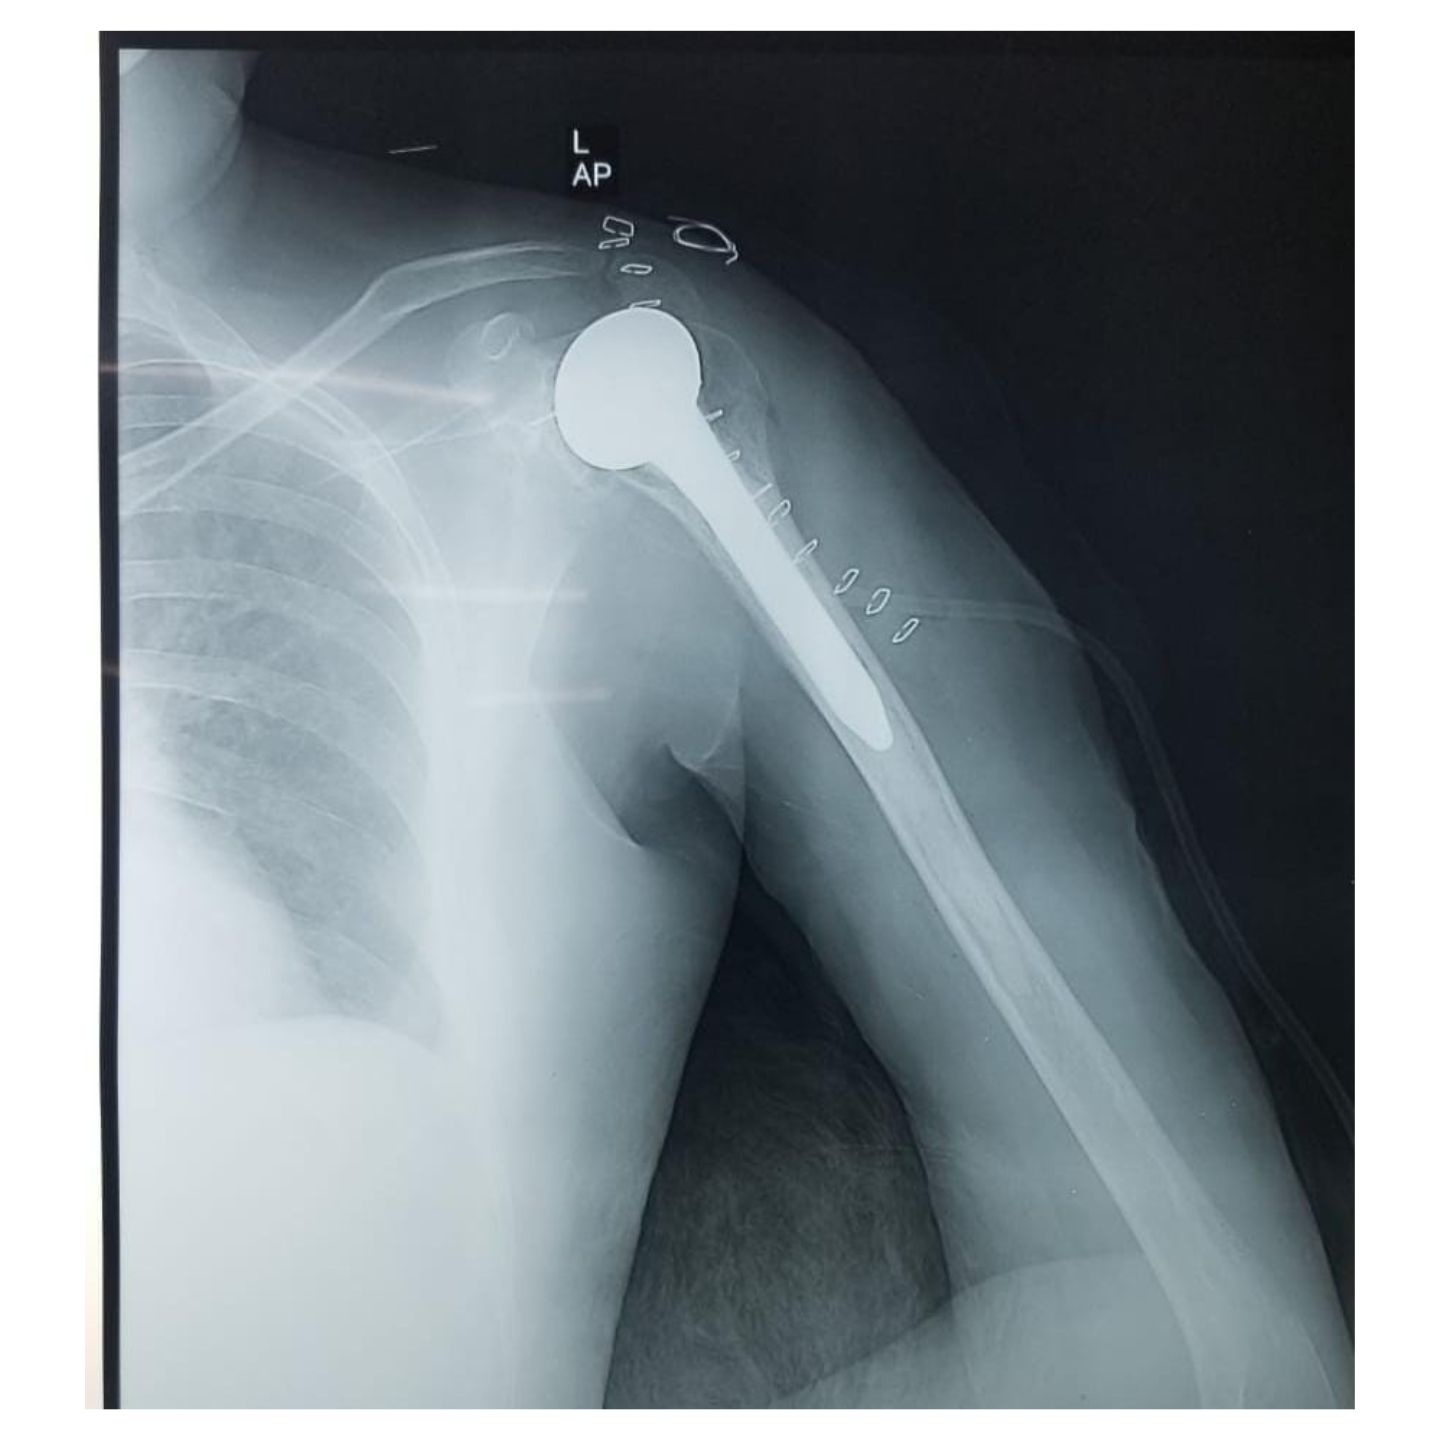

Anatomical Total shoulder arthroplasty